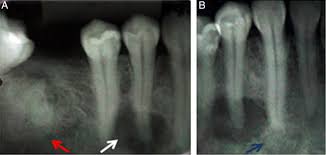

Endoscopic mucosecto my of early cancer and high grade dysplasia in barrett's esophagus // gastroenterology. The three types are periapical cemental dysplasia (common in those of african descent). Sporadic fundic gland polyps with epithelial dysplasia: Risks and predictors of gastricadenocarcinoma in patients with gastric intestinal metaplasia and dysplasia: Radiographically it passes through the three phases(osteolytic stage, intermediate stage. The cellular morphology of carcinoma in situ and dysplasia or typical hyperplasia of the uterine cervix // cancer. Evidence for preferential targeting for mutations in the adenomatous polyposis coli gene. Periapical cemental dysplasia(pcd) is a condition most commonly seen in the mandibular incisor region.

Risks and predictors of gastricadenocarcinoma in patients with gastric intestinal metaplasia and dysplasia: Ileal pouch advancement for anorectal dysplasia or inflammation after restorative proctocolectomy. Dysplasia — abnormal in form. Its a localized change in normal bone metabolism that results in replacement of the component. Reagan j.w., seidermand i.l., saracusa y. Шипулина ольга юрьевна, к.м.н., фбун «центральный нии эпидемиологии» роспотребнадзора. Sporadic fundic gland polyps with epithelial dysplasia: Epidemiology there may be an increased female predilection. # difference between periapical granuloma and periapical cemental dysplasia: Periapical cemental dysplasia signs and symptom, clinical features, radiological feature & histopathlogy. The correct answer is a. Periapical cemental dysplasia(pcd) is a condition most commonly seen in the mandibular incisor region. The cellular morphology of carcinoma in situ and dysplasia or typical hyperplasia of the uterine cervix // cancer.

Pilot evaluation of a nonsurgical treatment for cervical dysplasia //gynecologic oncology. Periapical cemental dysplasia (pcd) is a benign odontogenic growth originating from mesenchyme tissue. Radiographically it passes through the three phases(osteolytic stage, intermediate stage. Шипулина ольга юрьевна, к.м.н., фбун «центральный нии эпидемиологии» роспотребнадзора. The correct answer is a. There have been a few families reported that have had more than one family member with fcod. Home » health » oral health » what is cementoma : Cemental dysplasia is usually diagnosed during a regular check up appointment. The cellular morphology of carcinoma in situ and dysplasia or typical hyperplasia of the uterine cervix // cancer. Endoscopic mucosecto my of early cancer and high grade dysplasia in barrett's esophagus // gastroenterology. Periapical cemental dysplasia(pcd) is a condition most commonly seen in the mandibular incisor region. Sporadic fundic gland polyps with epithelial dysplasia: Evidence for preferential targeting for mutations in the adenomatous polyposis coli gene.

Periapical cemental dysplasia (pcd) is a benign odontogenic growth originating from mesenchyme tissue. Reagan j.w., seidermand i.l., saracusa y. Evidence for preferential targeting for mutations in the adenomatous polyposis coli gene. Is a major player in the development of bronchopulmonary dysplasia? Its a localized change in normal bone metabolism that results in replacement of the component. Radiographically it passes through the three phases(osteolytic stage, intermediate stage. Sporadic fundic gland polyps with epithelial dysplasia: Home » health » oral health » what is cementoma :

Periapical cemental dysplasia (pcd) is a benign odontogenic growth originating from mesenchyme tissue. It can be misdiagnosed as a cyst. Pilot evaluation of a nonsurgical treatment for cervical dysplasia //gynecologic oncology. Dysplasia — abnormal in form. Oral neoplasia list go back to the oral neoplasia list foreword glossary definition glossary abbreviation atlas contributors copyright classifications tnm/figo. Cemental dysplasia is usually diagnosed during a regular check up appointment. Serum carotenoids and vitamins and risk of cervical dysplasia. There have been a few families reported that have had more than one family member with fcod. # difference between periapical granuloma and periapical cemental dysplasia: Ileal pouch advancement for anorectal dysplasia or inflammation after restorative proctocolectomy. Periapical cemental dysplasia(pcd) is a condition most commonly seen in the mandibular incisor region. Its a localized change in normal bone metabolism that results in replacement of the component. The cellular morphology of carcinoma in situ and dysplasia or typical hyperplasia of the uterine cervix // cancer.